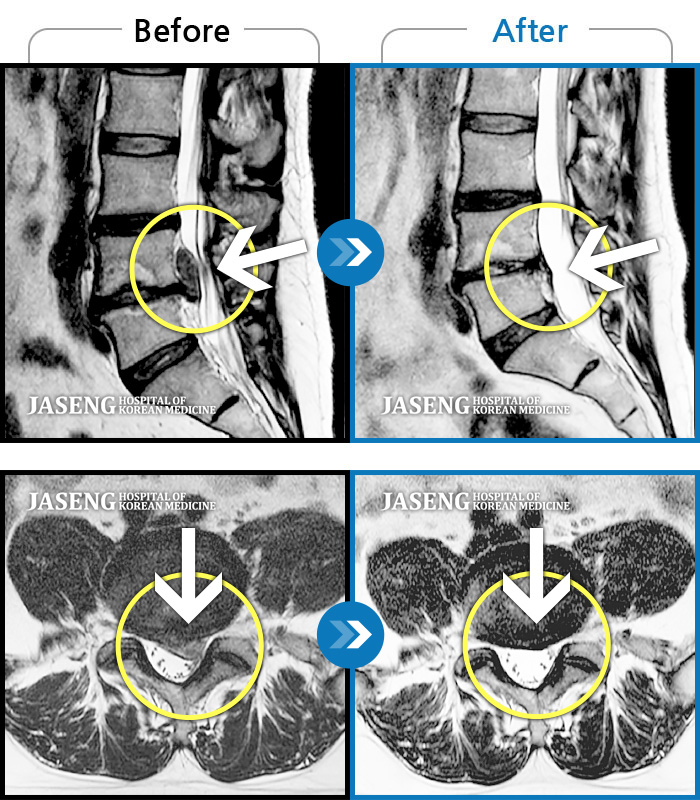

디스크에 입사한지 4년이 되었습니다. 추간판 탈출증이 처음 시작되었을 때 저림으로 인해 혼자 서거나 앉기가 어려웠고 왼쪽 다리와 골반 뒤쪽에 심한 통증과 저림이 있었습니다. 완전히 정상적인 삶을 사는 데 약 2년이 걸렸습니다. 그런데 최근에 다시 왼쪽 다리가 갑자기 저려서 오랜만에 얼굴이 보이는 성형외과를 찾았다.

앉아 있을 때 왼쪽 다리의 저림이 점점 심해지고 골반이 따끔거리기 시작했으며 허리까지 묵직한 느낌이 들었습니다. 견인을 하시는 분들도 계시겠지만 저는 정말 몸이 안 좋을 때만 주사를 맞고 정기적으로 물리치료와 충격파 치료를 받습니다.

아직 왼쪽 다리에 약간의 저림과 골반에 약간의 통증이 있지만 추간판 탈출증은 더 심해지지 않을 거라 믿고, 과하지 않고 꾸준히 꾸준히 하시면 좋아질 거에요. 당장 아프지 않으면 괜찮다고 생각하기보다는 규칙적인 운동과 올바른 자세, 스트레칭을 통해 장기적으로 몸을 건강하게 유지해야 할 때다. 아무것도 하지 않고 누워만 있는 시간을 보내지 않도록 노력하겠습니다.